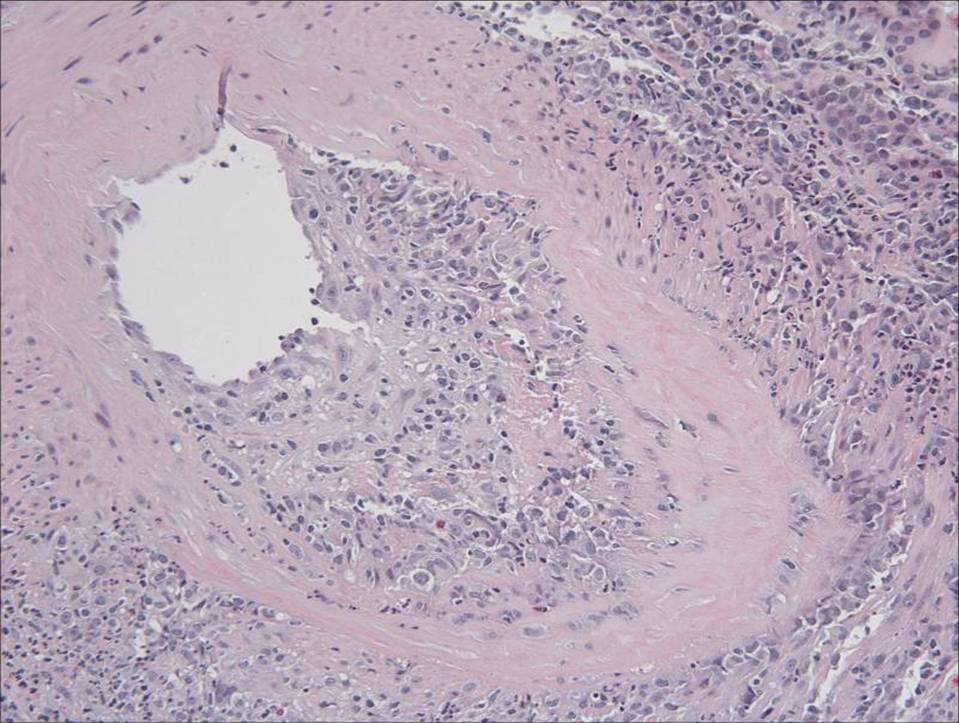

This is a two views of the same section of a medium-sized artery. There is massive infiltration of the vessel wall characteristic of a vasculitis -specifically this has the appearance of polyarteritis nodosa. There was significant fibrin deposition on IF within the walls of the vessel. There was also some mesangial deposition of IgG and IgM.

This is a fascinating case. First, this form of vasculitis is not usually associated with a positive ANCA test and this may have been a red herring. Second, the smaller vessels were normal and if the arcuate artery was not present on the specimen, this patient would likely have been diagnosed with an interestitial nephritis. The proteinuria in this case is probably a result of reduced tubular reabsorption given the fact that there is no significant glomerular disease. The low serum albumin was most likely due to GI losses rather than renal.